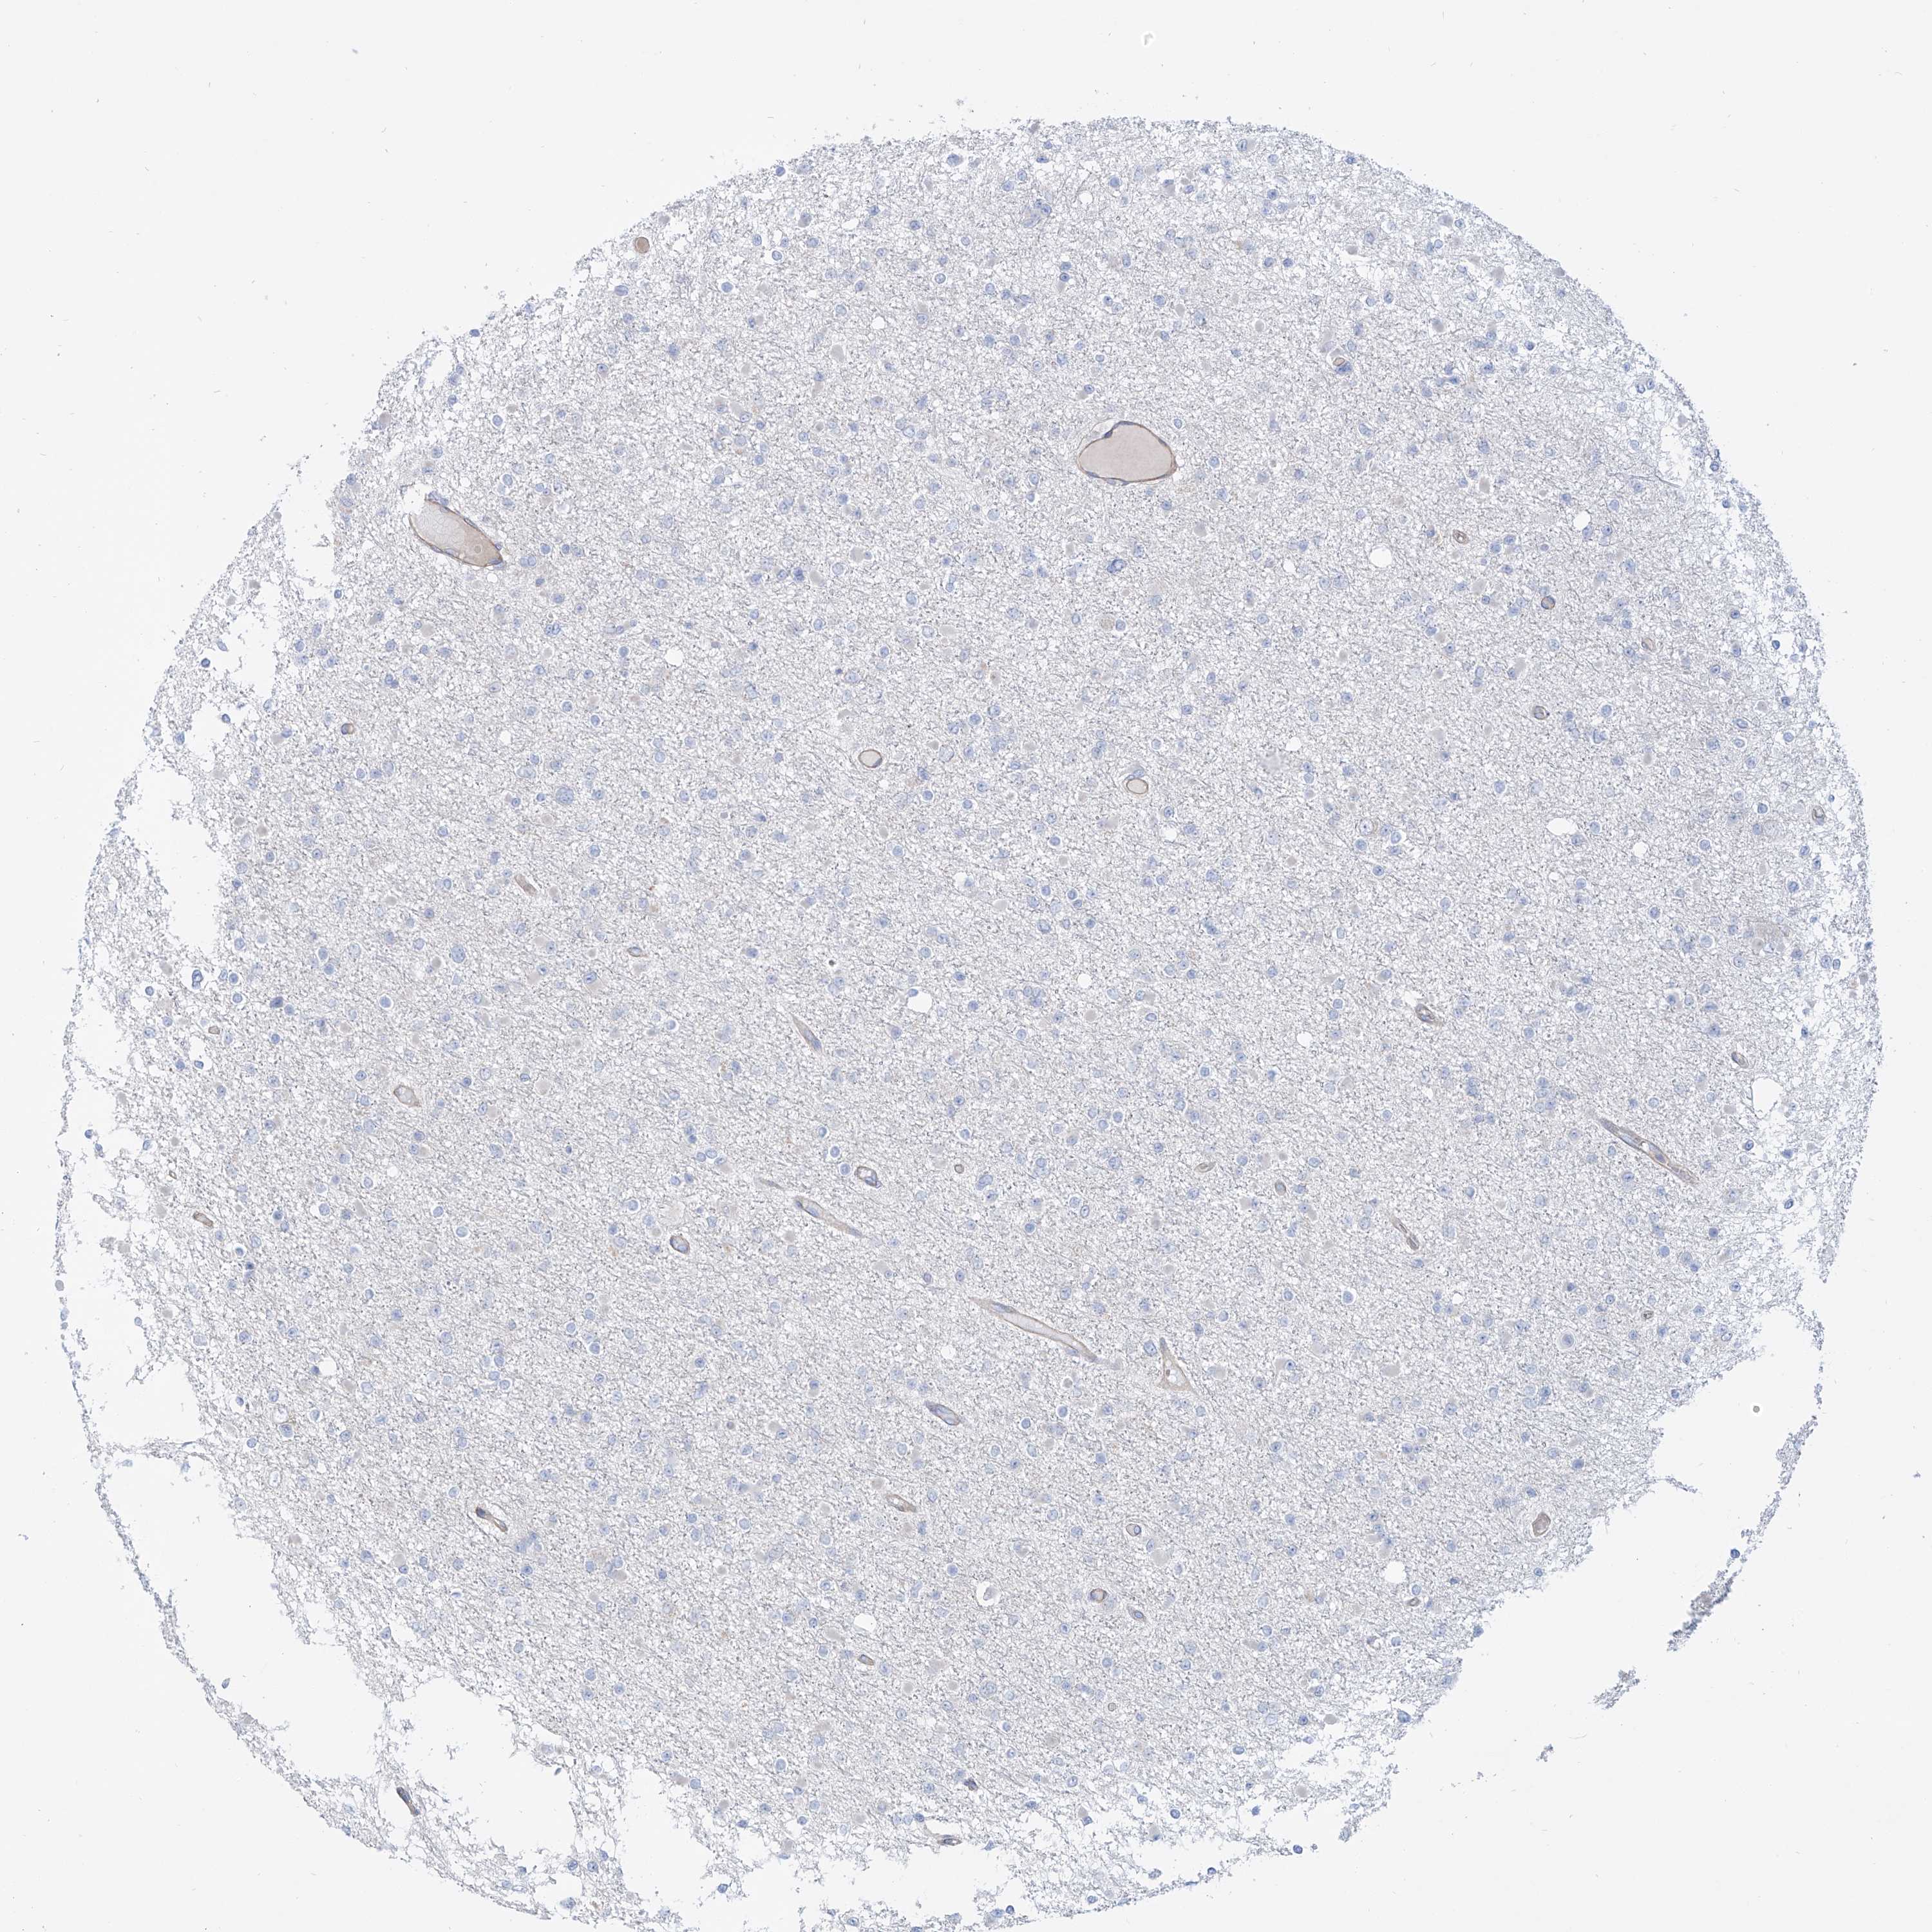

GLIOMA - Protein expressioni

A mouse-over function shows sample information and annotation data. Click on an image to view it in a full screen mode. Samples can be filtered based on level of antibody staining by selecting one or several of the following categories: high, medium, low and not detected. The assay and annotation is described here.

Note that samples used for immunohistochemistry by the Human Protein Atlas do not correspond to samples in the TCGA dataset.

Antibody stainingi

Antibody staining in the annotated cell types in the current human tissue is reported as not detected, low, medium, or high, based on conventional immunohistochemistry profiling in selected tissues. This score is based on the combination of the staining intensity and fraction of stained cells.

Each image is clickable and will lead to virtual microscopy that enables deeper exploration of all samples and also displays staining intensity scores, fraction scores and subcellular localization as well as patient and tissue information for each sample.

Antibody HPA031678

Staining

High

Medium

Low

Not detected

Intensity

Strong

Moderate

Weak

Negative

Quantity

>75%

75%-25%

<25%

None

Location

Nuclear

Cytoplasmic/membranous

Cytoplasmic/membranous,nuclear

Glioma, malignant, High grade

Glioma, malignant, Low grade

Glioblastoma, NOS